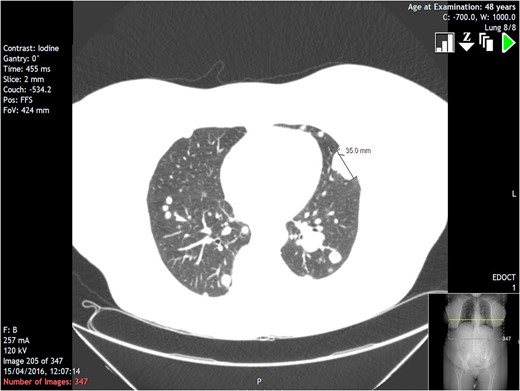

A 48-year-old lady was discovered to have multiple pulmonary nodules on chest x-ray (Fig. 1) which was taken in view of desaturating levels of oxygen post-operatively. The patient had undergone elective left leg varicose vein surgery. An urgent CT scan was subsequently booked and showed innumerable soft tissue lesions throughout both lung fields including a sub-pleural individual lesion measuring 3.5 cm in the lingula (Fig. 2). One lesion in the right upper lobe contained a small amount of air due to possible local erosion into an adjacent airway. Furthermore, a para-tracheal mass was seen on the right side measuring 5.6 cm with appearances suggestive of pleural metastases. Mediastinal nodes were reported as slightly prominent on the scan with nodes at the right hilum up to 12 mm in size.

Section from CT scan showing largest individual lung lesion in the lingula measuring 3.5 cm.